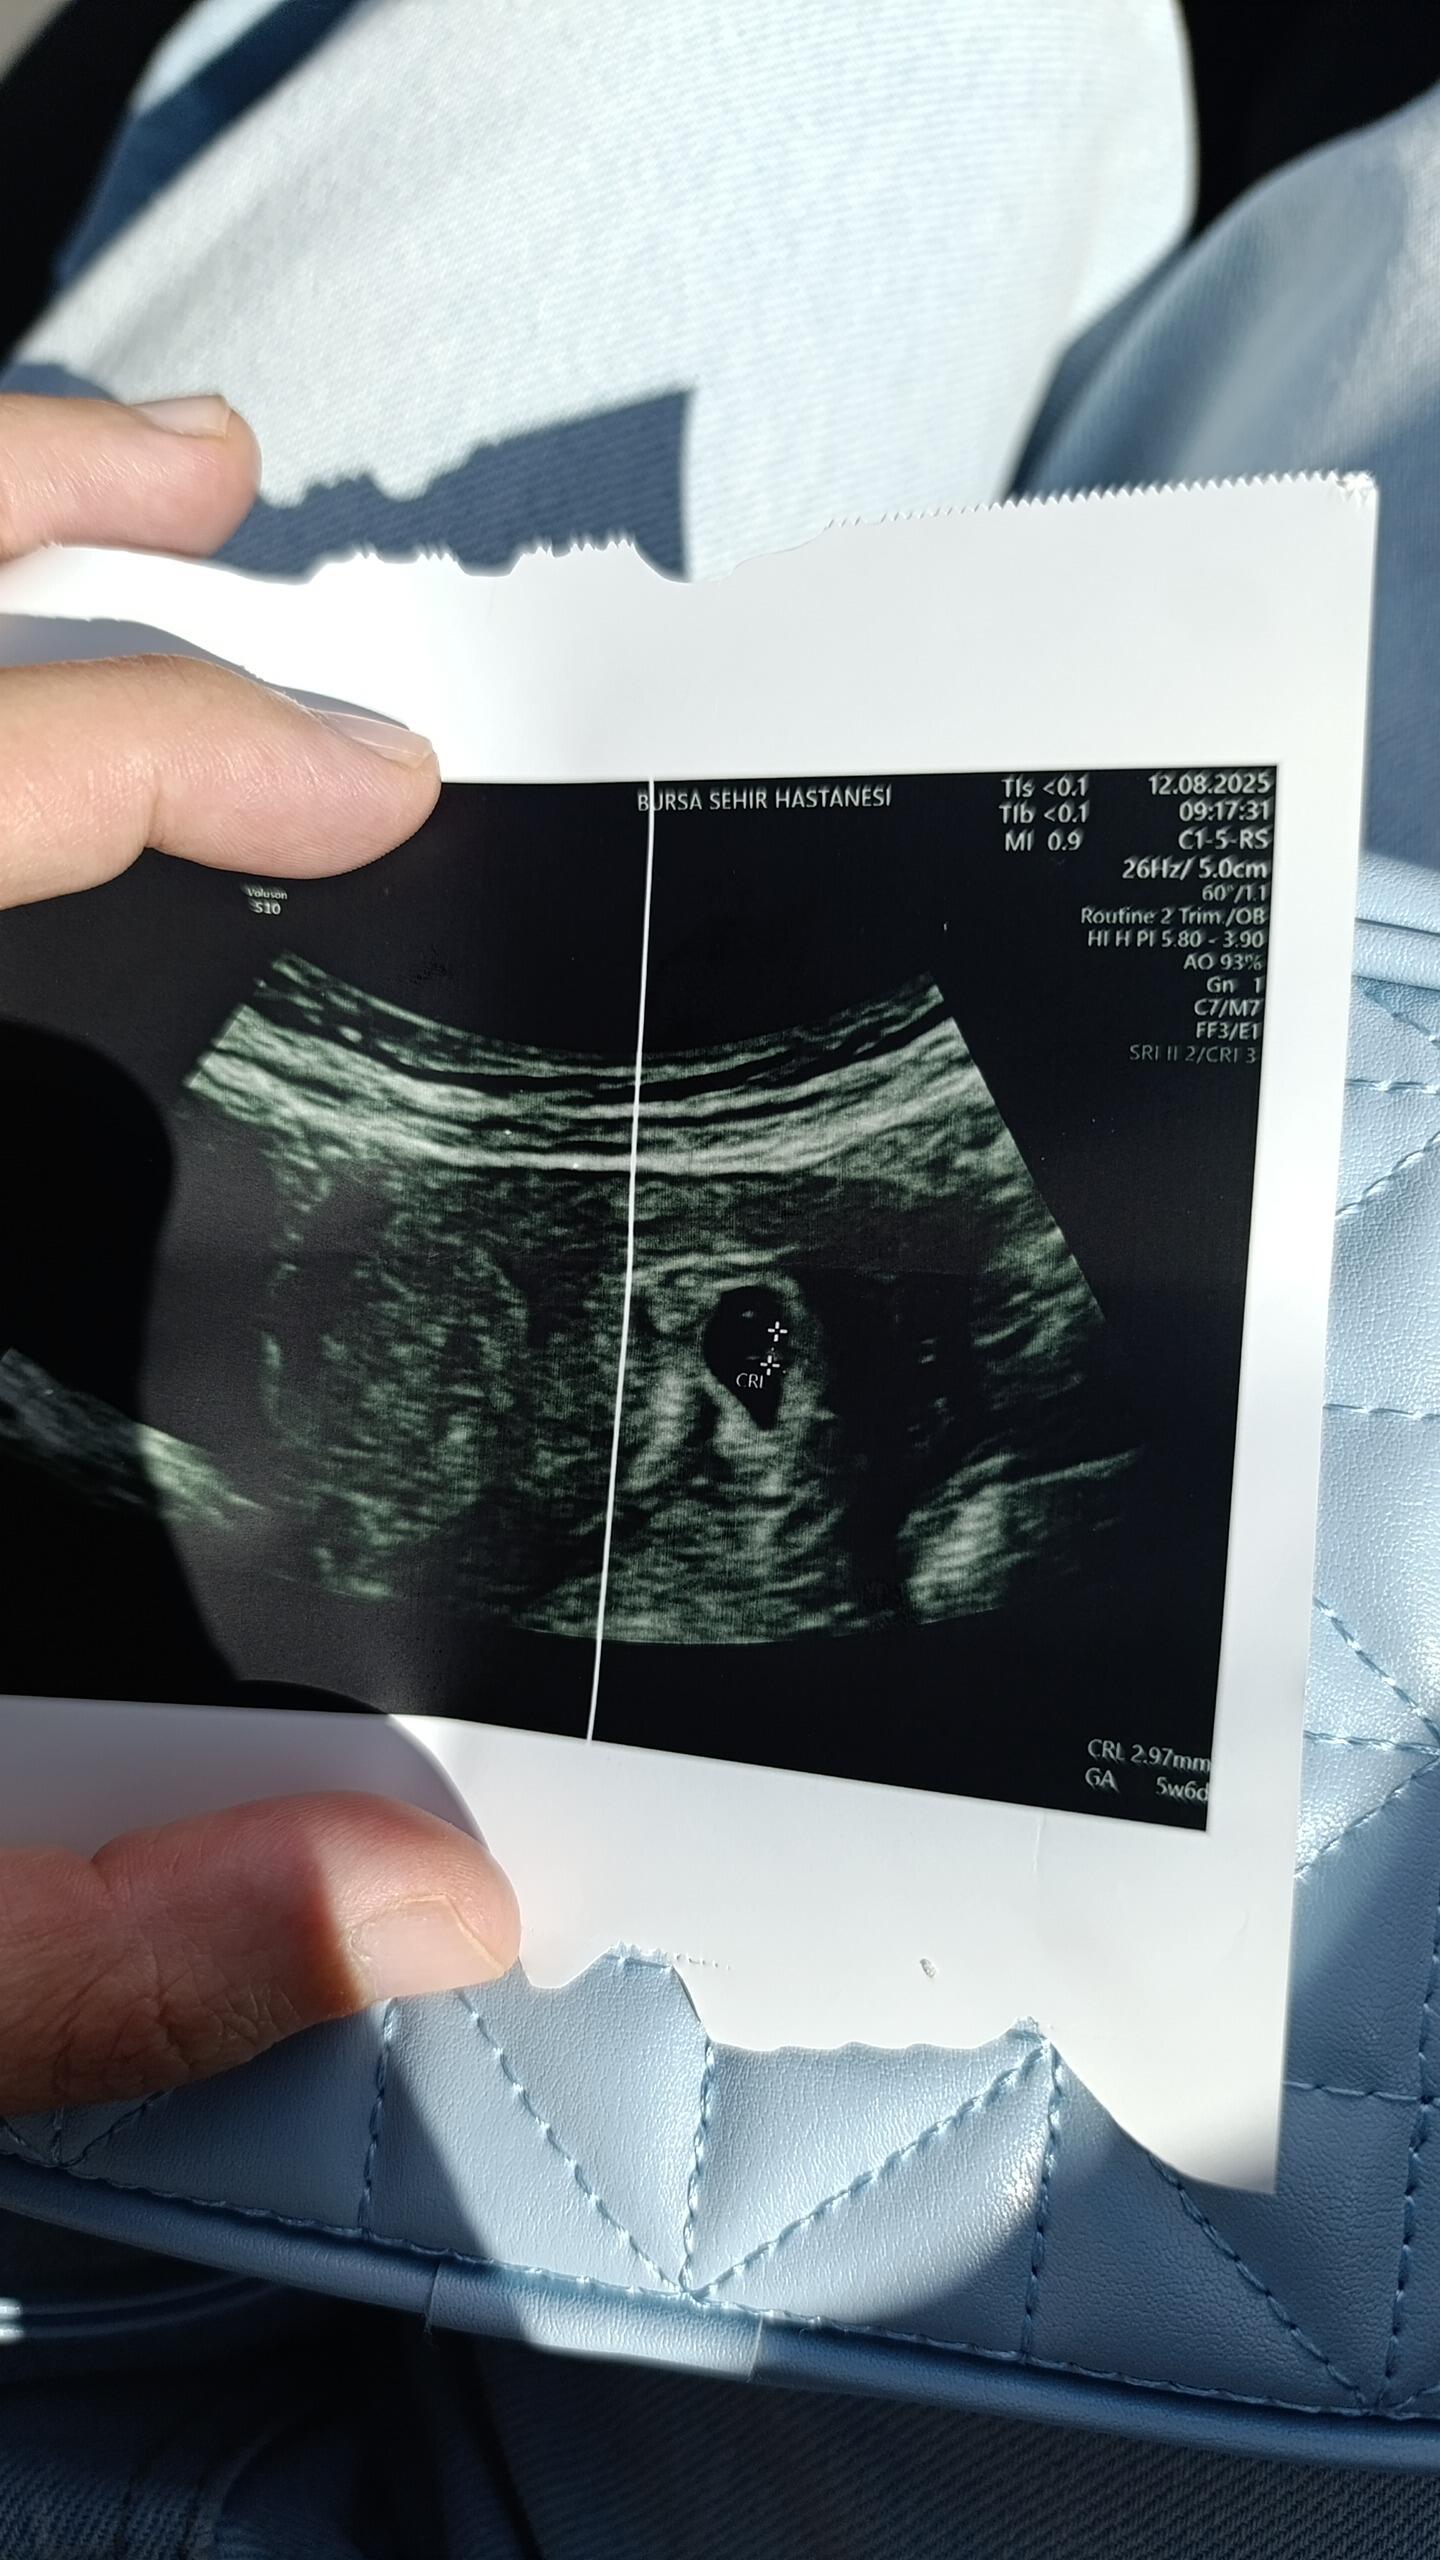

Tam bilmiyorum ama içi siyah olan kısım kese gibi görünüyor ama daha yeni gebelik sanırım embriyo gözükmüyor

Evet yenı gebelık bende dedım o ortadakı yuvarlak yolk mu acaba

Cnm kalp atışını duyabildinmi bende 5+5 haftalığım kalp atışını tam seçemiyorum haftaya gel dedi senin attığında da 5+6 yazıyo ondan merak ettim

Kuzum bugun tekrar gıttım haftasıyla uyumlu dedı ve kalp atısı baslamıs sukur